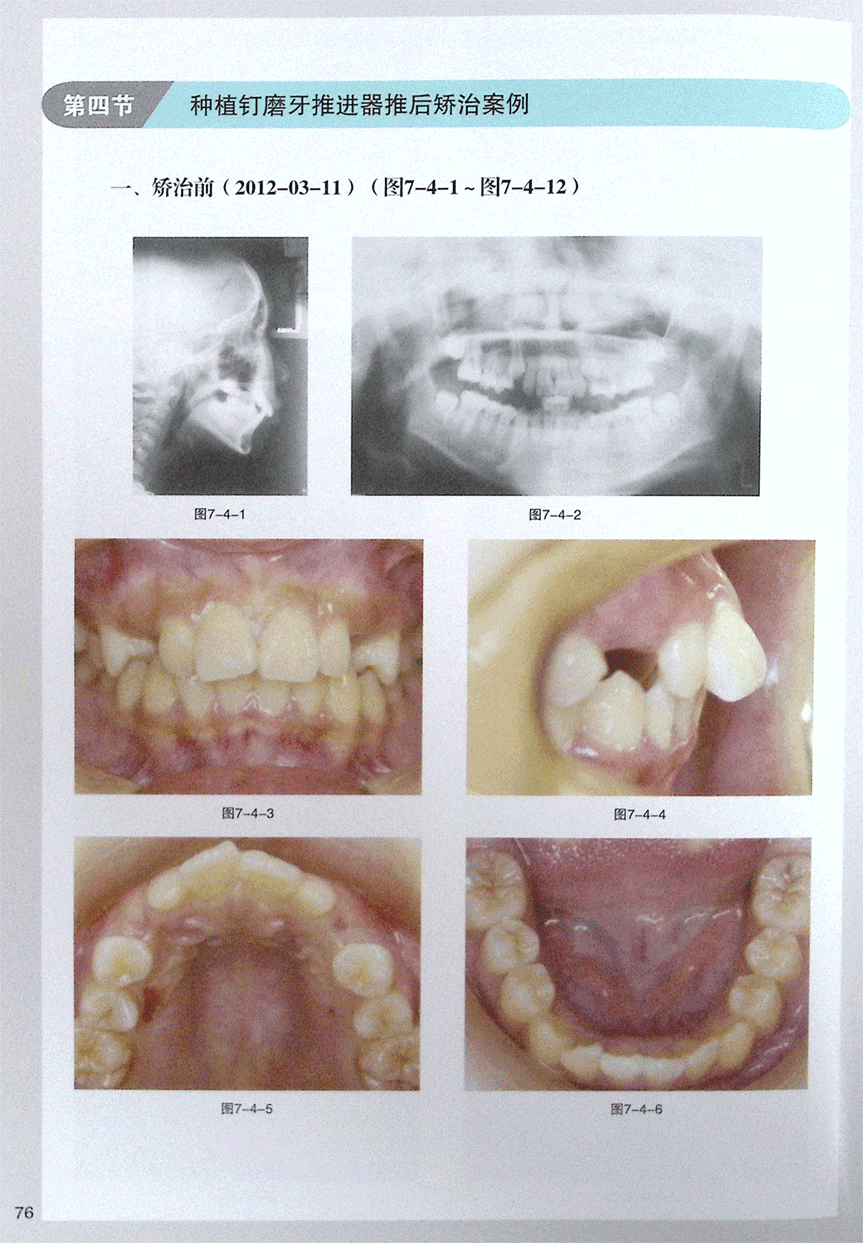

第四节 种植钉磨牙推进器推后矫治案例(1)